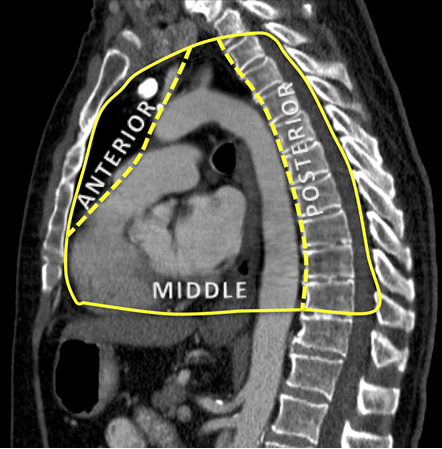

Carter BW, Benveniste MF, Madan R, et al. ITMIG classification of mediastinal compartments and multidisciplinary approach to mediastinal masses. Radiographics. 2017 Mar-Apr;37(2):413-36.Texto completo Resumo